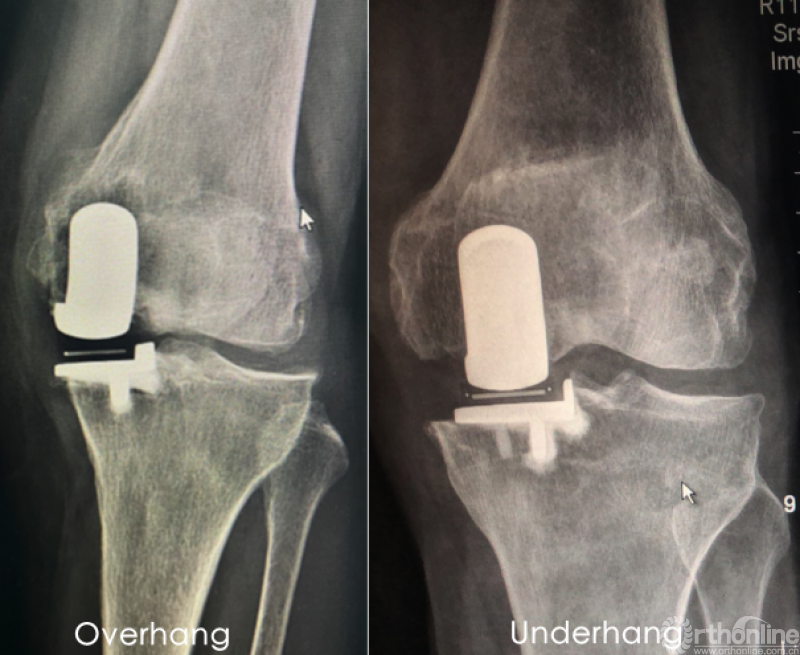

在UKA中,胫骨垂直截骨是决定胫骨内外对齐和旋转的最重要步骤。一方面,截骨偏内容易出现假体悬垂(overhang),即假体内侧突出胫骨内侧皮质,造成膝关节内侧软组织压力增大,出现术后持续疼痛;另一方面,胫骨垂直截骨偏外不仅容易损伤前交叉韧带(ACL),还容易出现假体覆盖不足(underhang),即假体内侧未覆盖到胫骨内侧皮质,使假体下沉的风险增大,最终导致假体翻修。